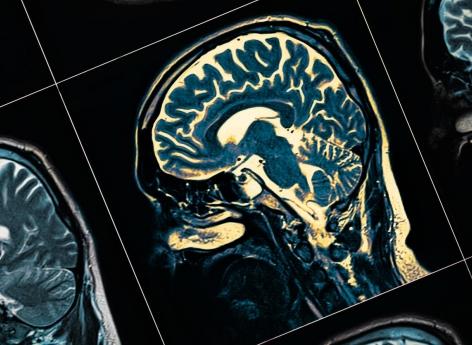

Touchant plus de 21 millions de personnes à travers le monde, la schizophrénie est une maladie mentale due à des perturbations qui affectent certaines fonctions du cerveau, notamment la pensée, les émotions et le comportement des personnes qui en sont atteintes. Les symptômes incluent des hallucinations, des délires, des troubles de la pensée, des sentiments, du comportement, de la perception et de la parole. Ils ont un impact important sur la vie sociale et quotidienne des personnes qui en sont atteintes.

Mais les chercheurs ont aussi découvert une nouvelle mutation : un changement de nucléotide unique dans un gène appelé PCDHA3 (Protocadherin Alpha 3), qui produit une une protéine jouant un rôle dans la création de connexions intercellulaires dans le cerveau.

Cette mutation génétique bloque directement l'action de cette protéine protocadhérine, identifiant un mécanisme possible par lequel les symptômes de la schizophrénie apparaissent.